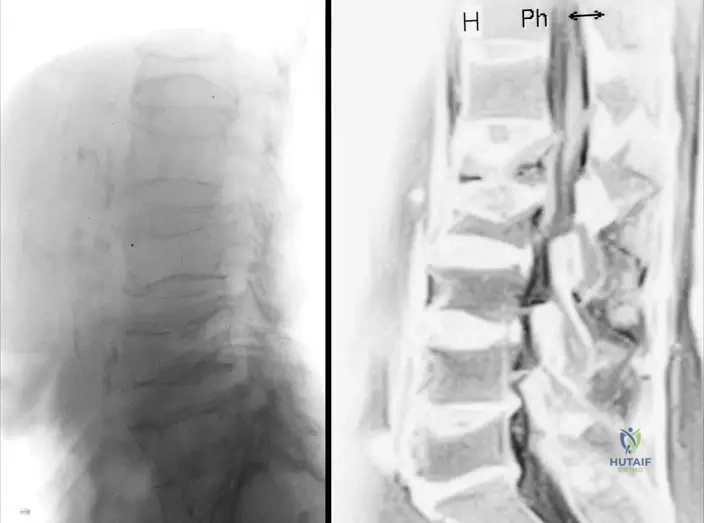

A genetic counselor is discussing the prognosis and recurrence risk for a couple whose child has a form of mesomelic dwarfism. The child presents with hip dislocation, clubhand, and short malformed fingers, and genetic testing reveals an autosomal recessive inheritance pattern.

View Answer & Explanation

Correct Answer: D

Rationale: The text describes Acro–coxo–mesomelic dwarfism as "autosomal recessive dwarfi sm, with hip dislocation, clubhand and foot, short malformed fi ngers, reduced articular mobility of elbows, clinodactyly, brachyrhizophalangia." This matches the clinical picture and inheritance pattern in the vignette. Nievergelt's and Langer types are autosomal dominant.

Question 38

A 3-year-old girl is diagnosed with a mesomelic dwarfism. Her parents are concerned about potential hip problems. On examination, she has short, malformed fingers and reduced elbow mobility. Radiographs show bilateral hip dislocations.

Rationale: The text specifically lists "hip dislocation" as a feature of Acro–coxo–mesomelic dwarfism, which is distinct from the features listed for Nievergelt and Langer type. While "reduced articular mobility of elbows" is mentioned for Acro-coxo-mesomelic, "deformities of the elbow joints" is listed for Nievergelt/Langer, making hip dislocation a clearer distinguishing feature.

A pediatrician observes a 2-year-old child with disproportionate short stature. The child's forearms and lower legs appear significantly shorter than the upper arms and thighs.

Correct Answer: C

Rationale: The term "mesomelic" refers to the middle segments of the limbs, specifically the forearms (radius and ulna) and the lower legs (tibia and fibula). This is consistent with the definition of mesomelic dwarfism as an elective defect of the mesial segments.